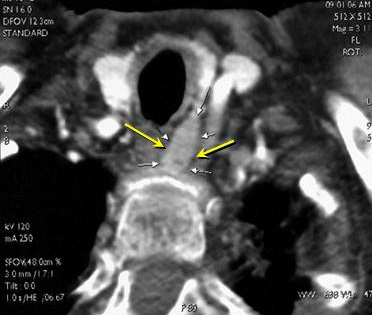

Иллюстрации и схемы по остеопорозу и паращитовидной железе